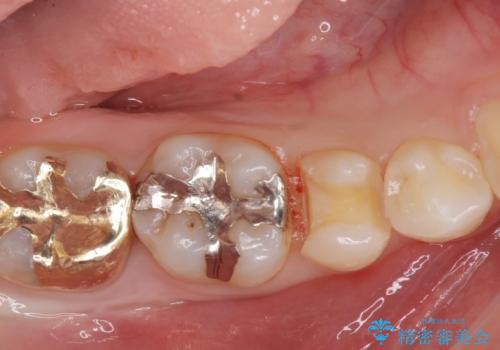

治療した歯は過去に樹脂で治療されていて、虫歯が再発していました。

樹脂の治療は経年的に劣化し、また歯質との隙間ができて虫歯の再発リスクが高いです。

e-max(セラミック)の治療は劣化をせず、歯質との隙間もできないため虫歯の再発のリスクが低いです。